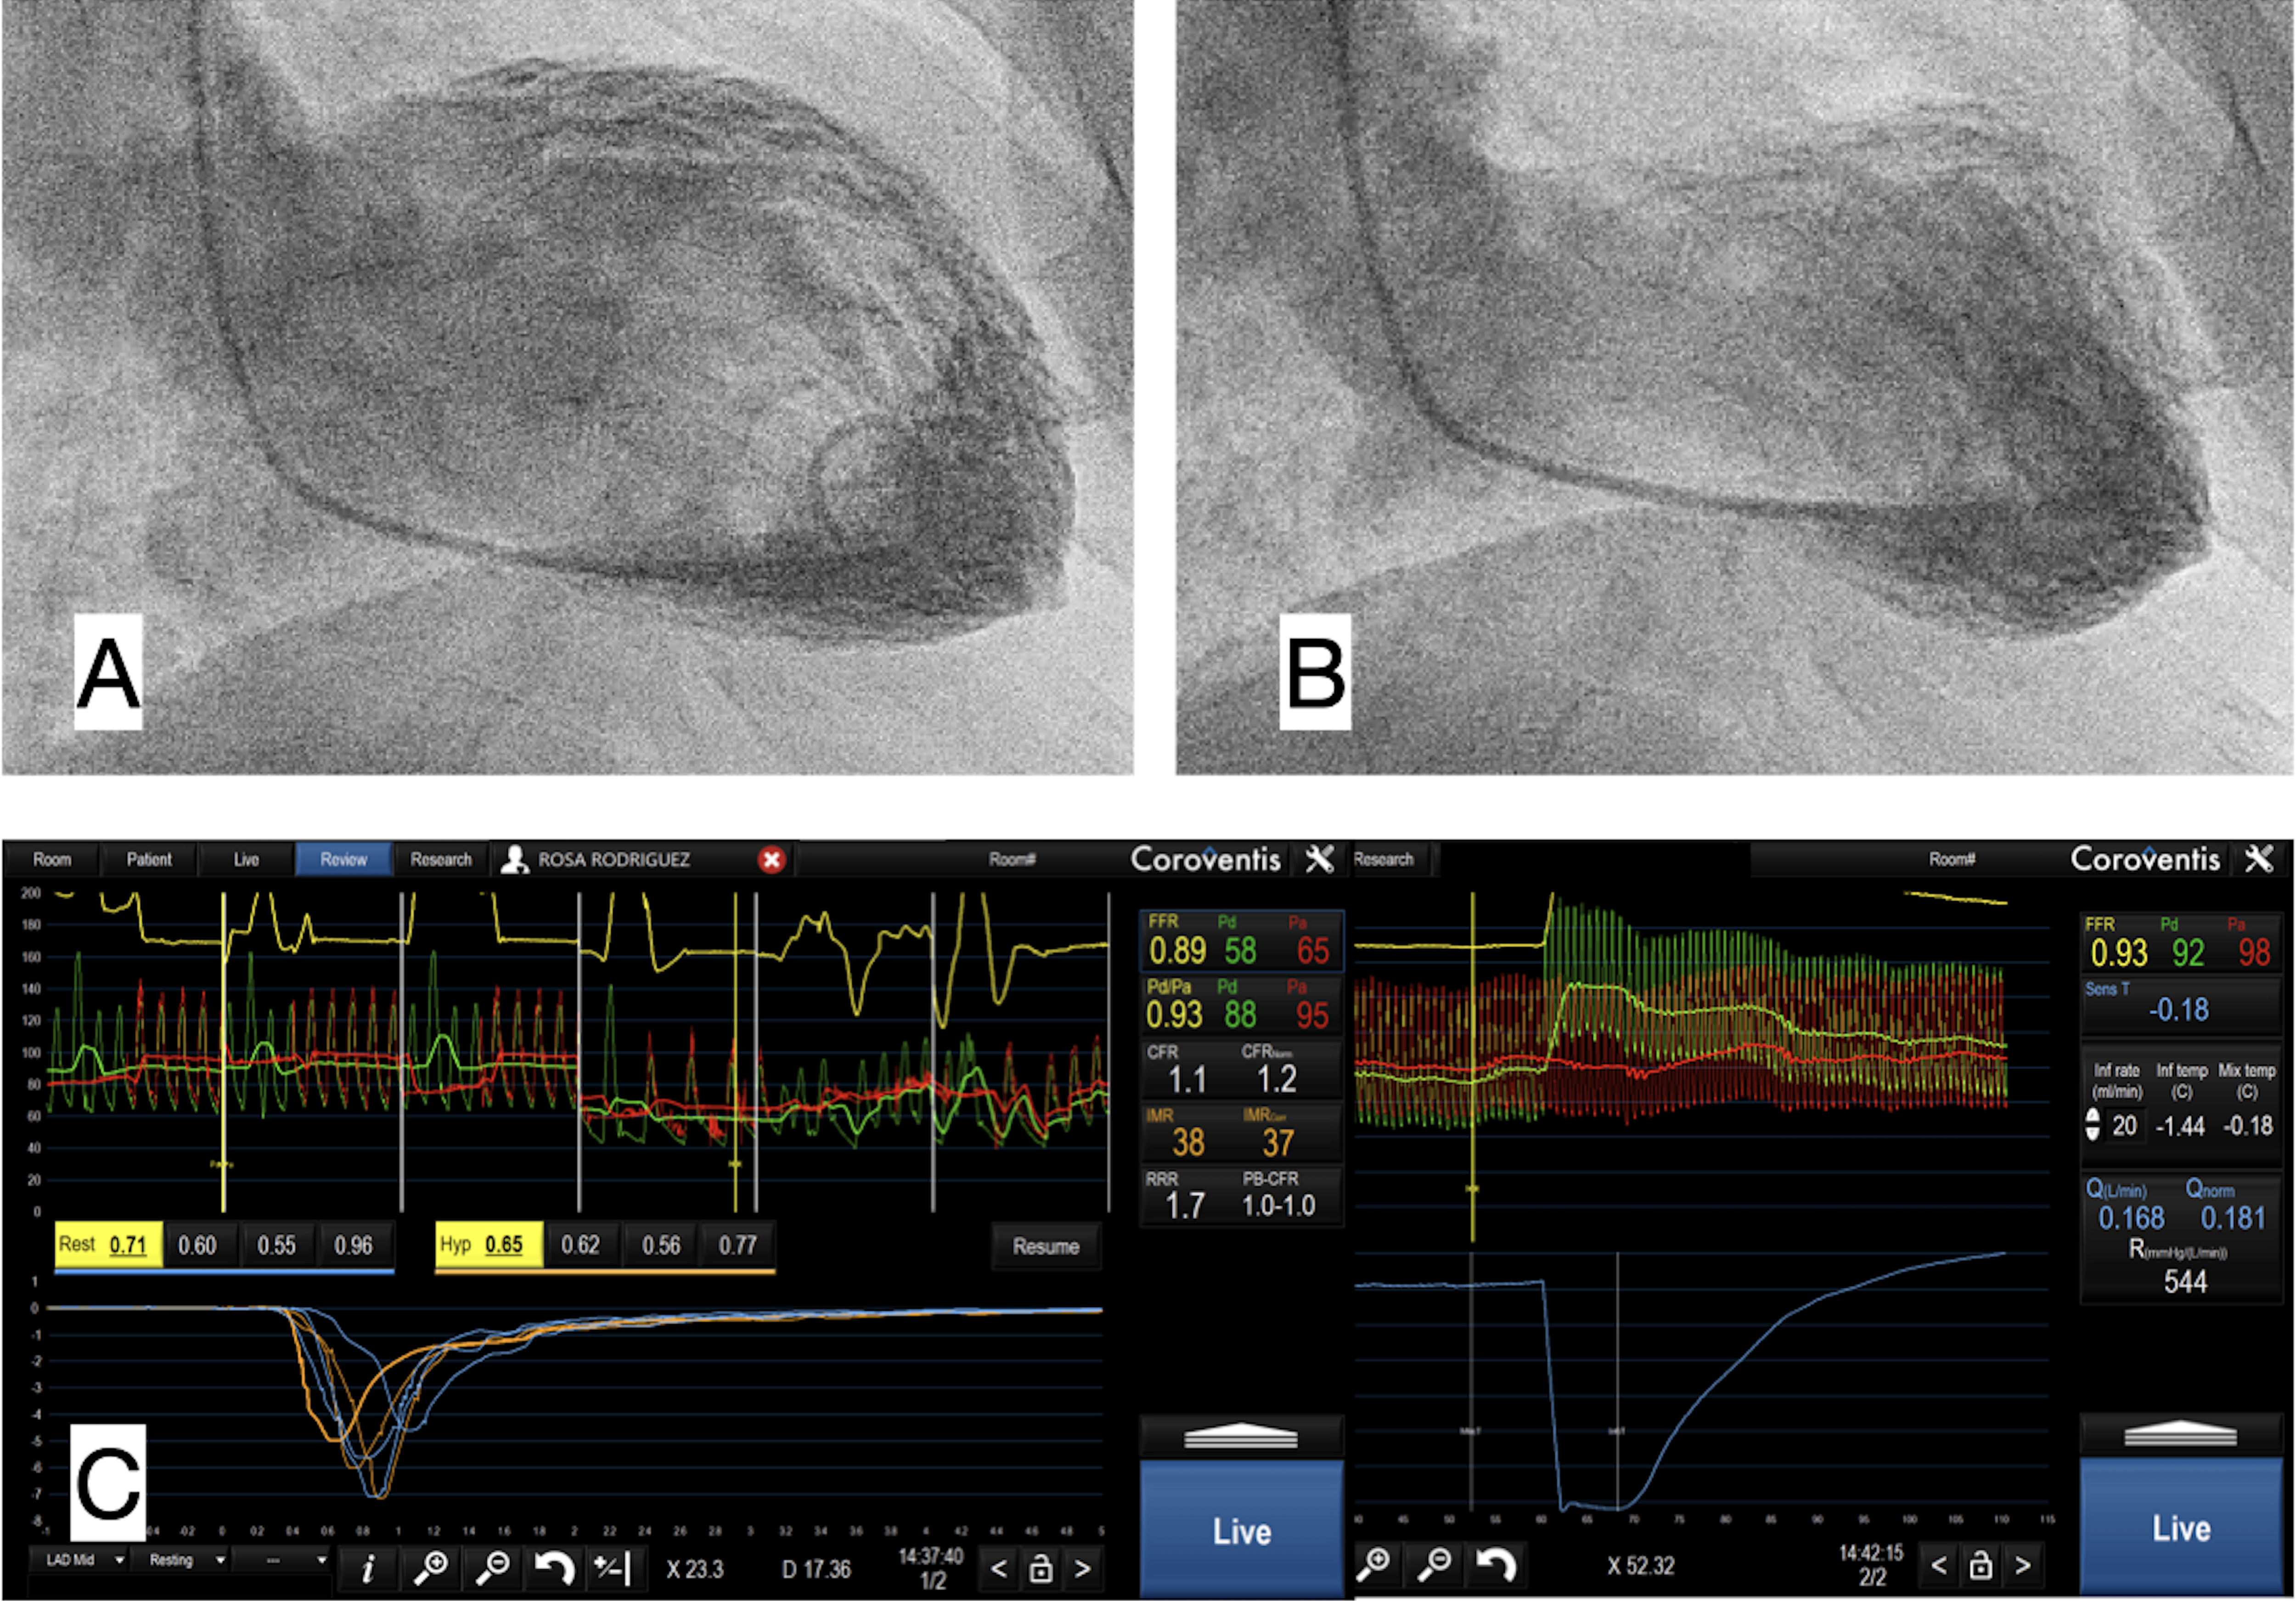

LV wall motion abnormality are multipole, including: hypokinesia, akinesia, apical dyskinesia, or apical ballooning with basal hyperkinesia, with a classical image of Japanese octopus trap (Fig. 1A,B) [3].

Fig. 1.Ventriculography and coronary physiology in Takotsubo Syndrome. (A) Ventriculography in telediastole. (B) Ventriculography in telesystole, with apical akinesia or apical ballooning. (C) Coronary invasive physiology in Left Anterior Descending coronary artery with Fractional Flow Reserve (FFR) 0.89, Coronary Flow Reserve (CFR) 1.1, Index of Microcirculatory Resistance (IMR) 38, meaning low coronary flow with high microvascular resistances without epicardial coronary lesions.